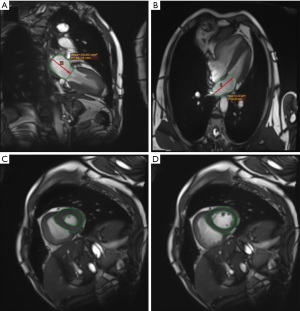

The RV end-diastolic ventricular area to LV end-diastolic ventricular area (RVEDA/LVEDA), a promising and easily derived metric from the standard four-chamber view of the CMR (Figure 3), holds significant diagnostic value in PH. At a cutoff >0.96, this parameter demonstrates 75% sensitivity and 100% specificity for detecting pre-PH, with an AUC of 0.93 (33).

The ventricular mass index (VMI), defined as the ratio of RV mass to LVMM, demonstrates robust diagnostic and prognostic utility in PH. VMI showed good correlation with mPAP (50,66,67), and VMI ≥0.45 for diagnosing PAH showed 85% sensitivity and 82% specificity (50). Apart from its effectiveness as a standalone PH diagnostic, VMI performs well in diagnostic modeling. A study with 97 non-PH populations and 506 PH patients developed a model predicting mPAP based on VMI, septal angle, and black blood slow-flow score, achieving an AUC of 0.95 for diagnosing PH (51). In predicting prognosis, Rajaram et al. demonstrated a significant correlation between VMI and mortality in connective tissue disease-associated PAH (CTD-PAH) [hazard ratio (HR) =5.56, P=0.013] (50).

The interventricular septal angle, the angle between the apex of the ventricular septum and the upper and lower insertion points of the ventricular septum (68) (Figure 4A,4B), serves as both a diagnostic and prognostic marker in PH. A study has shown (52) that interventricular septal angle predicts combined pre-PH and post-PH with an AUC of 0.911. In addition, the interventricular septal angle predicts all-cause mortality in PH, which is of prognostic value. It was shown (53) that the interventricular septal angle was an independent predictor of mortality in PH-HFpEF (HR =1.48, P<0.001), and the resulting CMR prognostic model, which was based on interventricular septal angle and VMI, predicted mortality in patients with PH-HFpEF with an AUC of 0.76 (P<0.001).

Other parameters reflecting septal deformation include septal LV displacement duration and septal curvature. Septal LV displacement duration is defined as the proportion of cardiac cycle frames showing leftward septal deviation, which was confirmed to be an independent predictor of clinical worsening in patients with pre-PH (54). A study of 37 patients with suspected PH showed (55) that septal curvature was significantly correlated with pulmonary artery systolic pressure (PASP) (r=0.77, P<0.001). When the interventricular septum is curved to the left, PASP may be higher than 67 mmHg.